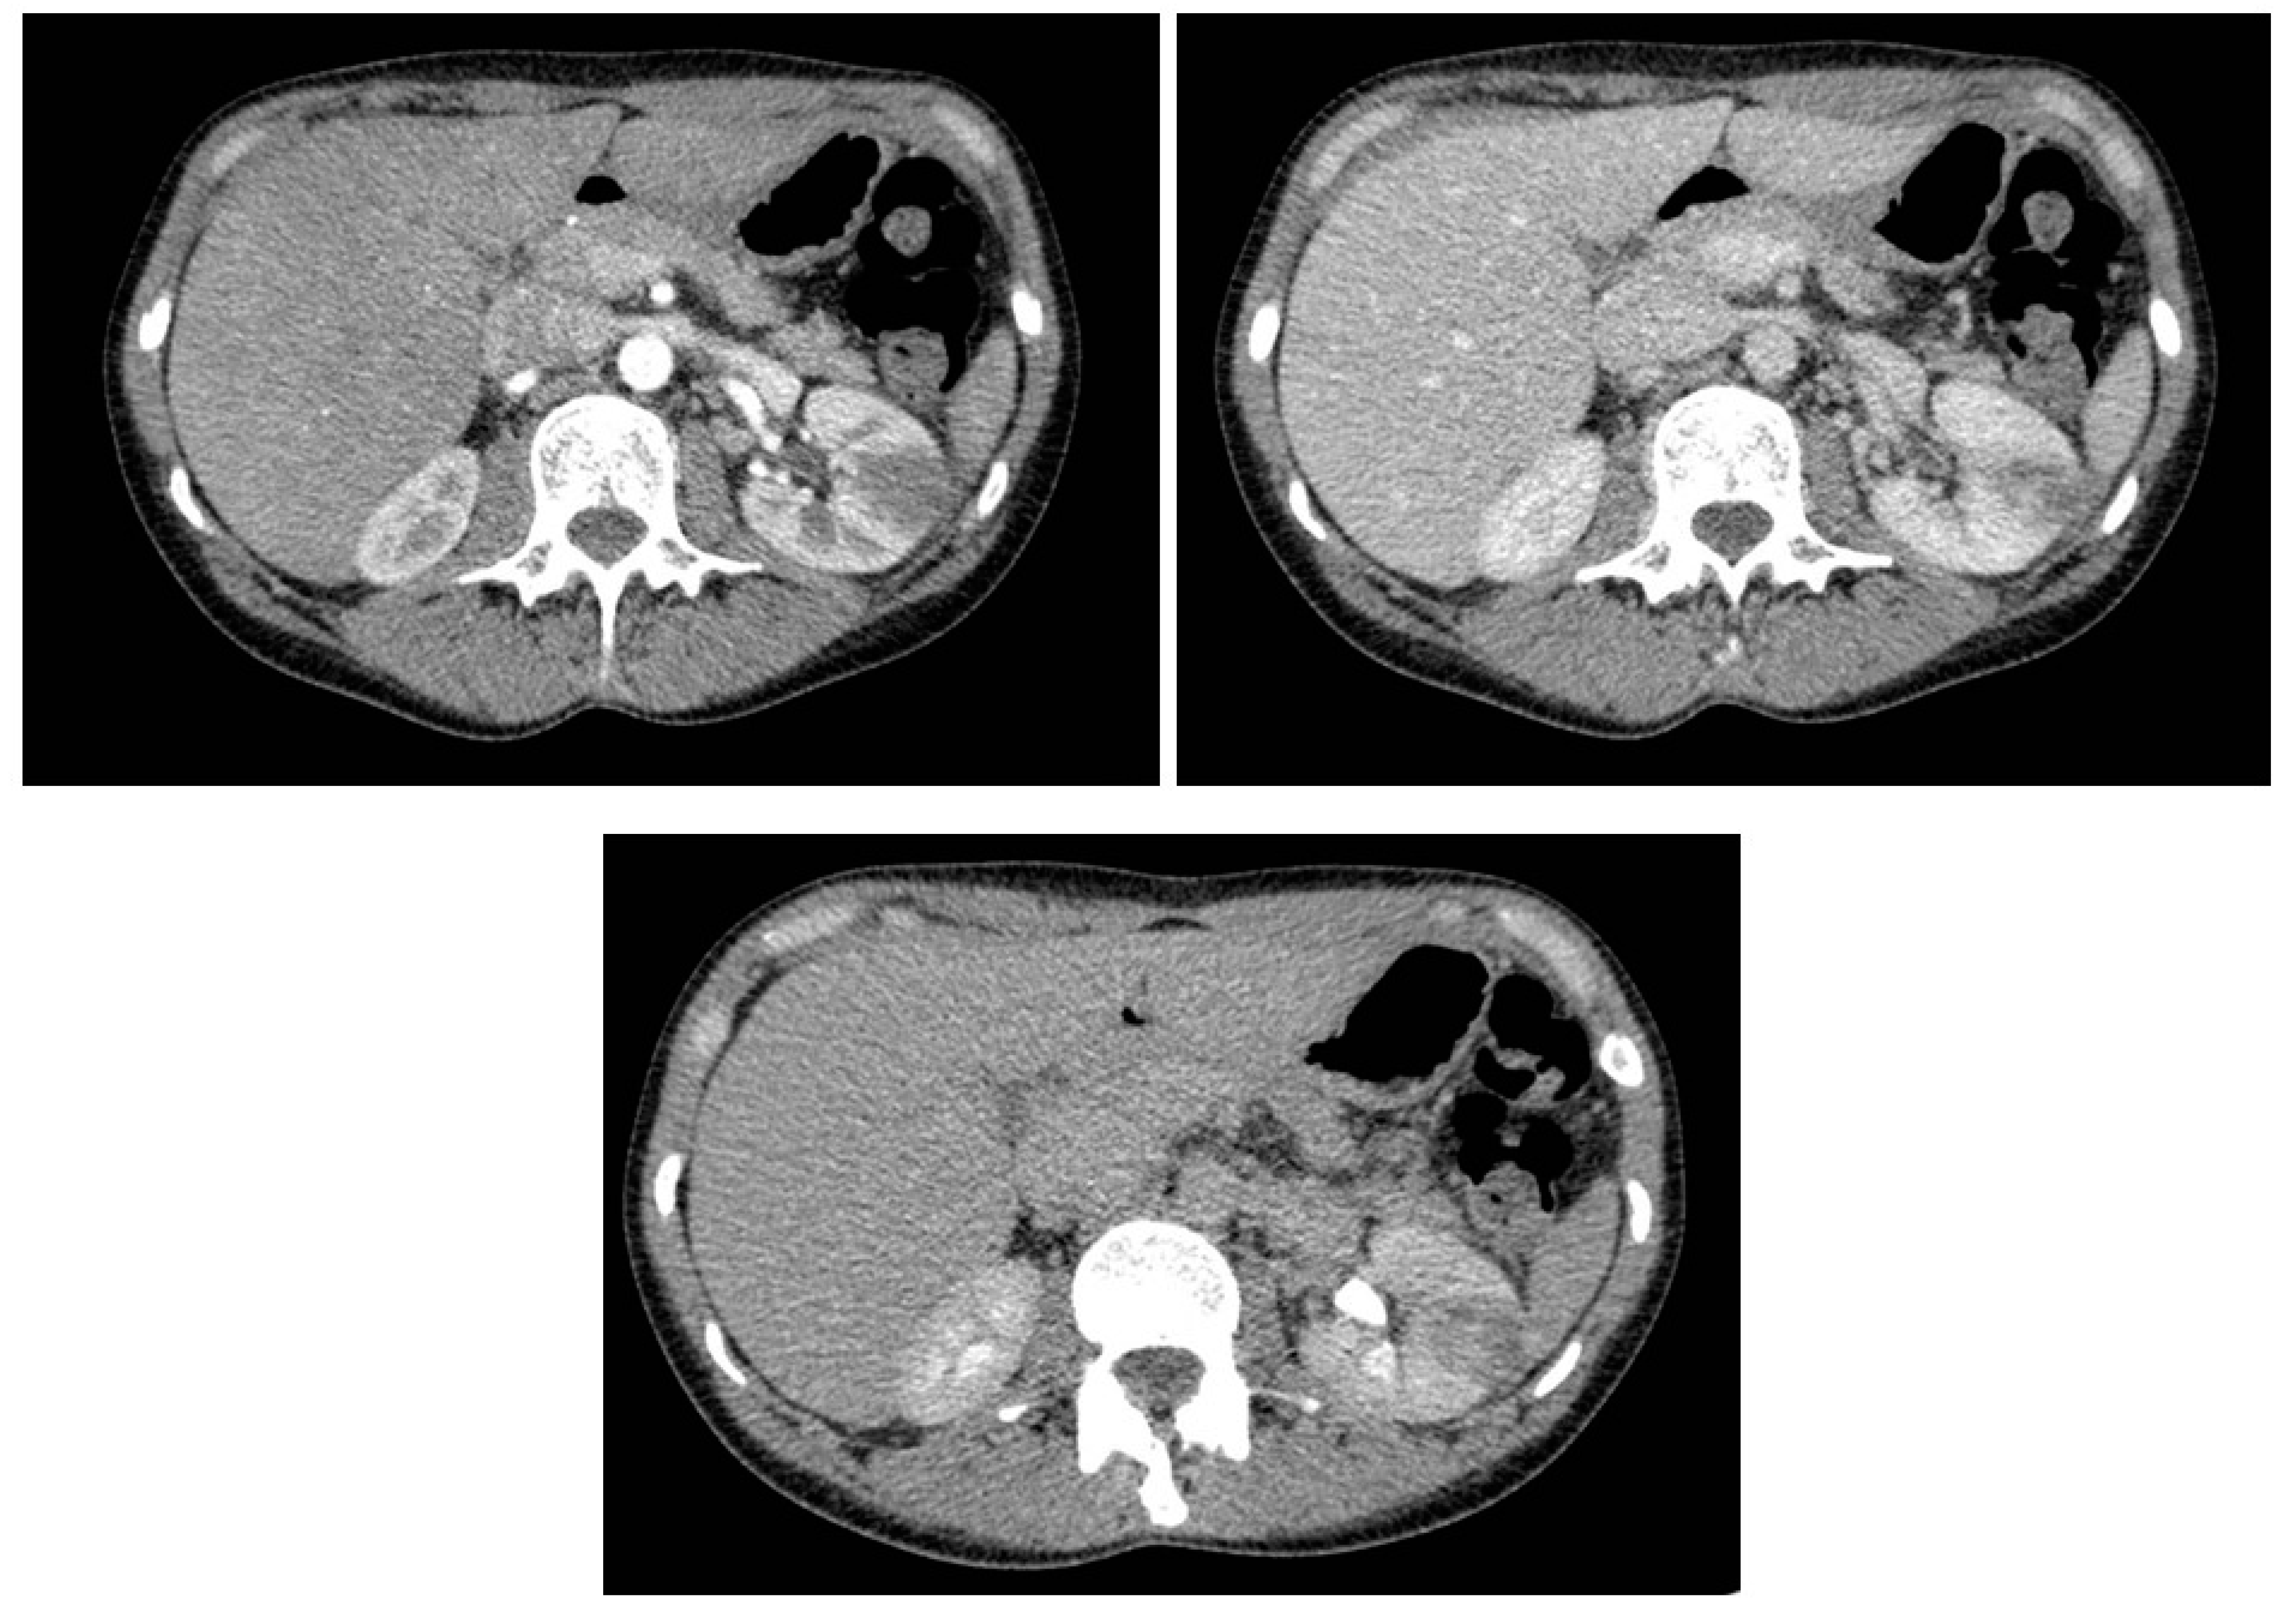

- Rinaldo, C.; Grimaldi, D.; Di Serafino, M.; Iacobellis, F.; Verde, F.; Caruso, M.; Sabatino, V.; Orabona, G.D.; Schillirò, M.L.; Vallone, G.; et al. An update on pyelonephritis: Role of contrast enhancement ultrasound (CEUS). J. Ultrasound 2023, 26, 333–342. [Google Scholar] [CrossRef]